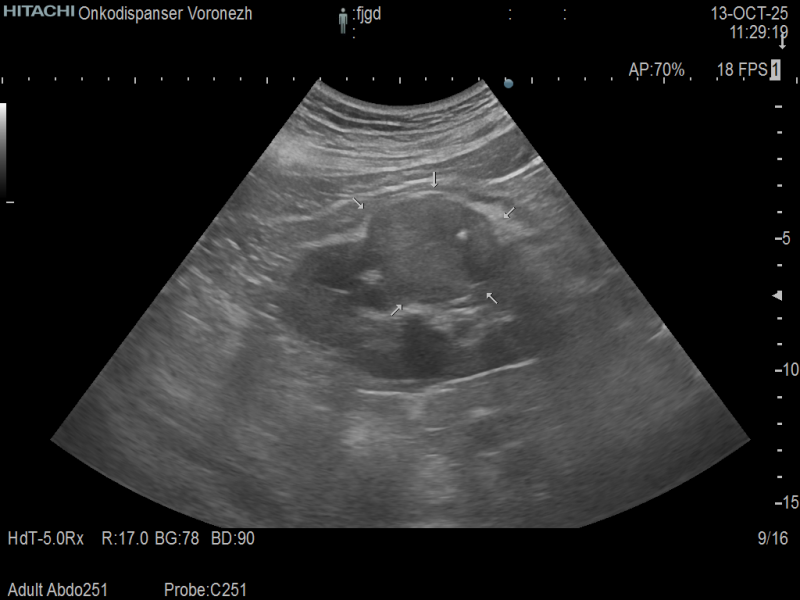

- Ультразвуковое исследование